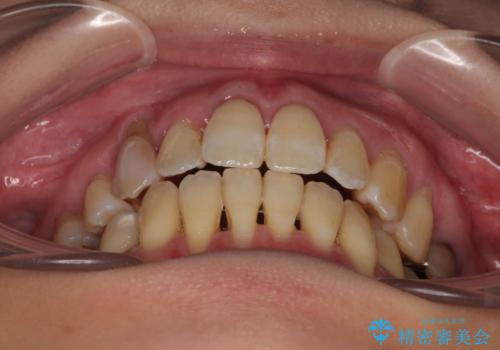

- 前歯のデコボコと唇の閉じにくさを気にして来院された患者様です。

上顎骨よりも下顎骨の幅が広く、更には下顎骨が左側に変位していたため、より良い咬み合わせを達成することを目的として、急速拡大装置を用いて上顎骨を拡大することとしました。

デコボコが強い上に、口元の突出感も気にしていたため、上下左右の小臼歯4本を抜歯して、ワイヤー装置にて矯正治療を行うこととしました。

歯根露出が顕著であったため、歯の移動は早く、スムーズに治療を終えられるかと思いましたが、歯槽骨が硬く、治療は長期間に及びました。

過剰に力をかけ続ける事態となり、一部の歯では変色したり、神経が失活したりとトラブルが続きました。

それでも当初とは比べものにならないほど、綺麗な歯列に仕上げることができました。